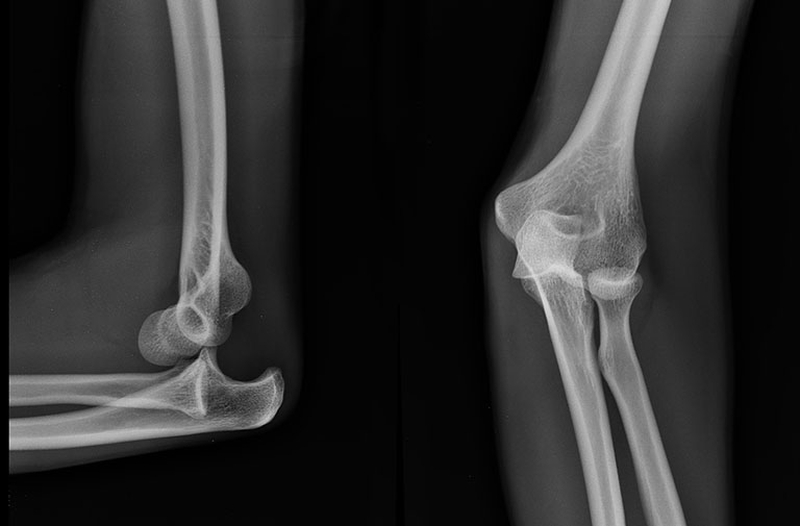

Trật khớp khuỷu tay trẻ em - Chấn thương cực kỳ nguy hiểm

Trẻ em là đối tượng rất dễ bị tổn thương bởi ở độ tuổi nhỏ các cơ quan và các bộ phận trên cơ thể của trẻ vẫn chưa phát triển hoàn thiện. Chúng rất dễ bị ảnh hưởng bởi các tác động từ bên ngoài môi trường. Trong số các chấn thương mà trẻ có thể gặp phải thì trật khớp khuỷu tay được xem là chấn thương phổ biến và thường gặp nhất. Vậy chấn thương này có nguy hiểm hay không? Hãy cùng chúng tôi tìm hiểu kỹ hơn về trật khớp khuỷu tay trẻ em cũng như cách xử lý khi trẻ bị trật khớp khuỷu tay thông qua bài viết này.

Trật khớp khuỷu tay là gì?

Khớp khuỷu tay được xem là một trong những khớp lớn của cơ thể con người. Khớp khuỷu tay giúp cho con người có thể dễ dàng thực hiện các thao tác như gập, duỗi và sấp ngửa cẳng tay một cách dễ dàng.

Trật khớp khuỷu tay trẻ em là tình trạng khớp khuỷu tay của trẻ bị kéo lệch và trượt ra khỏi vị trí ban đầu. Trật khớp khuỷu tay sẽ khiến cho trẻ khó cử động, không thể sinh hoạt một cách bình thường. Thậm chí nếu bị nặng còn có thể kèm theo gãy xương, đứt dây chằng…